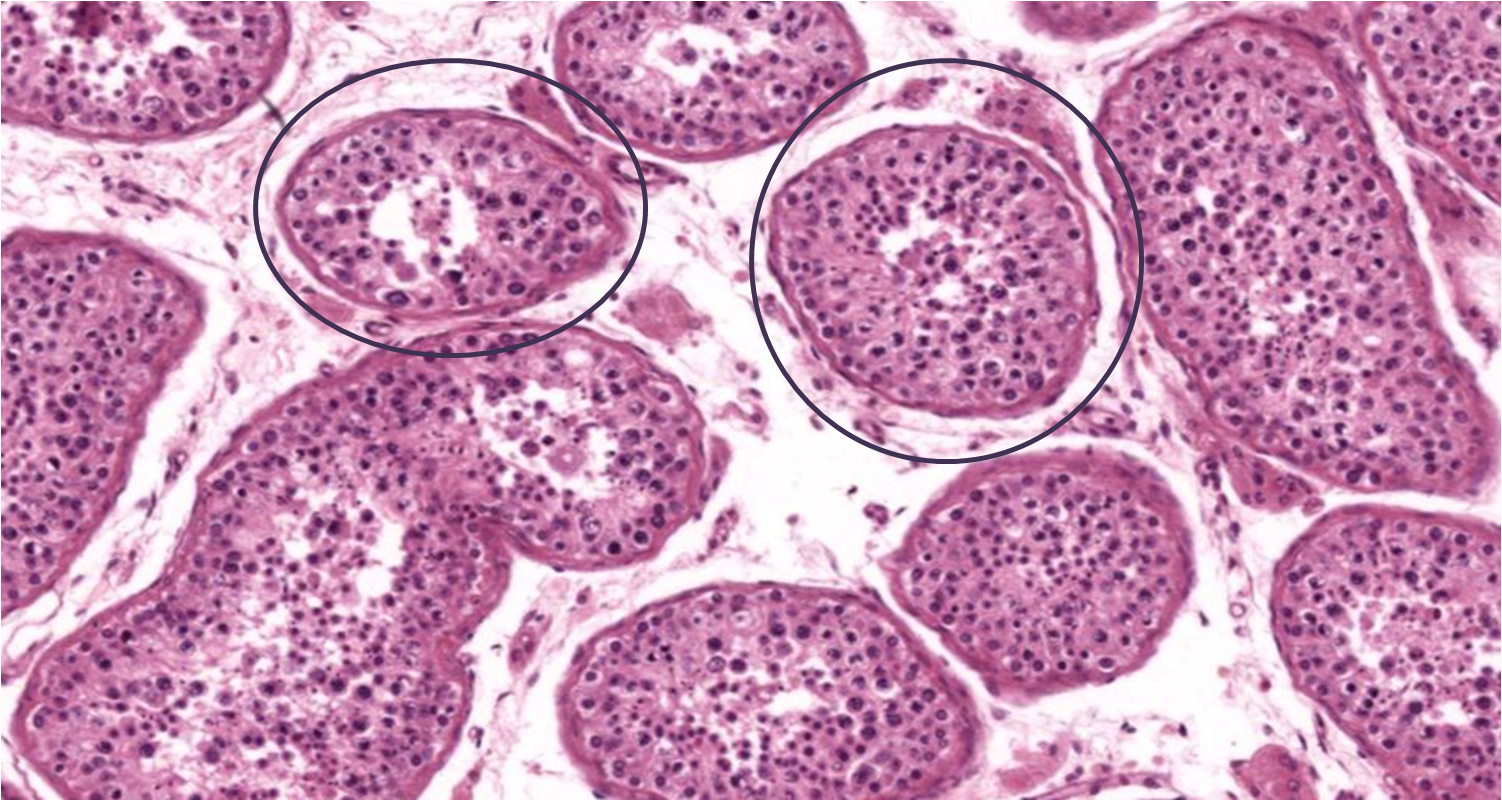

Testículo

Túmulos seminiferos